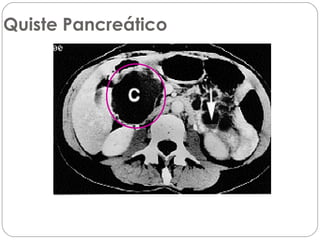

Quiste Pancreático

• Pseudoquiste: formación de densidad líquida caracterizada por la

existencia de una pared de tejido fibroso o granulatorio que

aparece no antes de las 4 semanas desde el inico del cuadro.